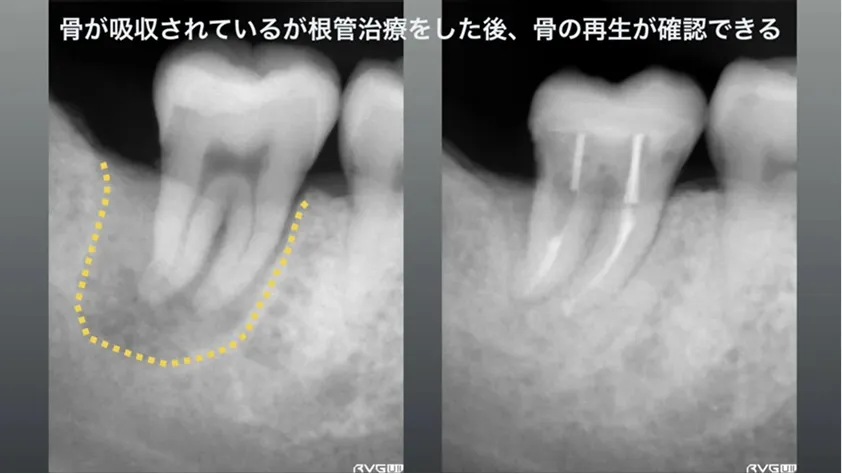

外科的歯肉療法後予後が悪くても

通常の根管治療で治すことができます

他院で以前、外科的歯内療法をを行ったが予後が悪く、虎ノ門吉松歯科医院に来院。

長くて太いメタルポスト(レントゲン上では白い部分)が確認でき、別な歯科医院では長いメタルポストは取れないと言われて来院、術前黄色の点線部分は大きく骨が吸収して、口腔内では時々腫れを繰り返す症状があるとのこと。

通常の根管治療を2回行い、数ヶ月後には骨再生がレントゲン上で現れ、外科をやらなくても通常の根管治療で虎ノ門吉松歯科医院では治す事が可能です。